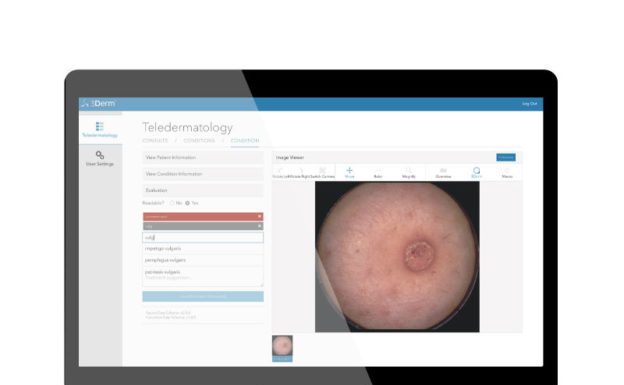

據外媒 CISION 消息,近日 AI 創業公司 3Derm 宣布,旗下檢測皮膚癌的產品 3DermSpot 人工智慧成像系統,獲得兩項 FDA 突破性設備認定。